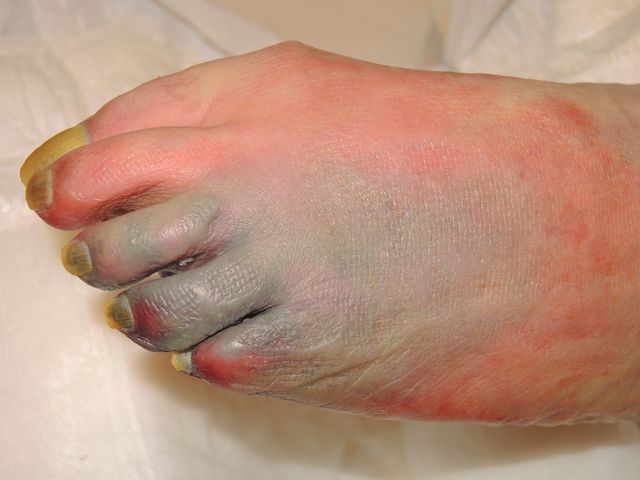

Necrosis por isquemia aguda.

Necrosis por isquemia aguda